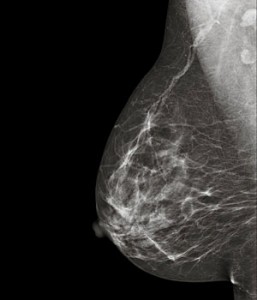

El cáncer de mama es uno de los tumores más comunes en las mujeres pero, gracias a la tecnología, hoy es muy fácil detectarlo a tiempo y detener su avance. La manera más eficaz para combatir contra este tipo de cáncer es someter las mamas a un escrutinio regular que permita detectar posibles nódulos o partes duras. Además, cada cierto tiempo, también es recomendable someterse a la mamografía o termografía, que garantizan una mayor precisión.

Por esta razón, los investigadores le recomiendan a las mujeres que no tienen un historial familiar de cáncer de mama, que no se sometan a un examen genético puesto que las probabilidades de que dé negativo son elevadas y estimularían la adopción de hábitos de vida poco saludables, incrementando así, el riesgo. En otras palabras: como el examen genético no es una prueba que puede predecir con exactitud el cáncer de mama, lo mejor es mantener un estilo de vida sana y apostar por las pruebas tradicionales, como la mamografía.